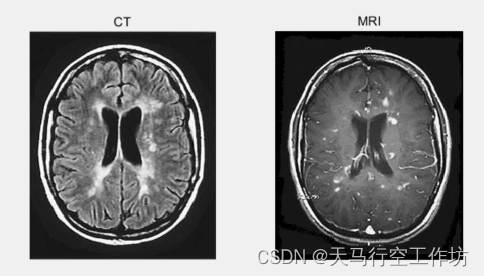

ct/mri融合是现代医学中的图像信号融合中最为常见的一种融合模式。ct颅脑图像的组织密度大和分辨率高,显示人体骨质清晰;而mri的颅脑软组织密度分辨率好,对人体颅脑组织结构信息显示得更加清晰。如何同时利用好两种图像优势,帮助医生快速诊断,是目前医学界研究热点之一。

本文介绍一种基于小波分解的CT和和MRI图融合方法